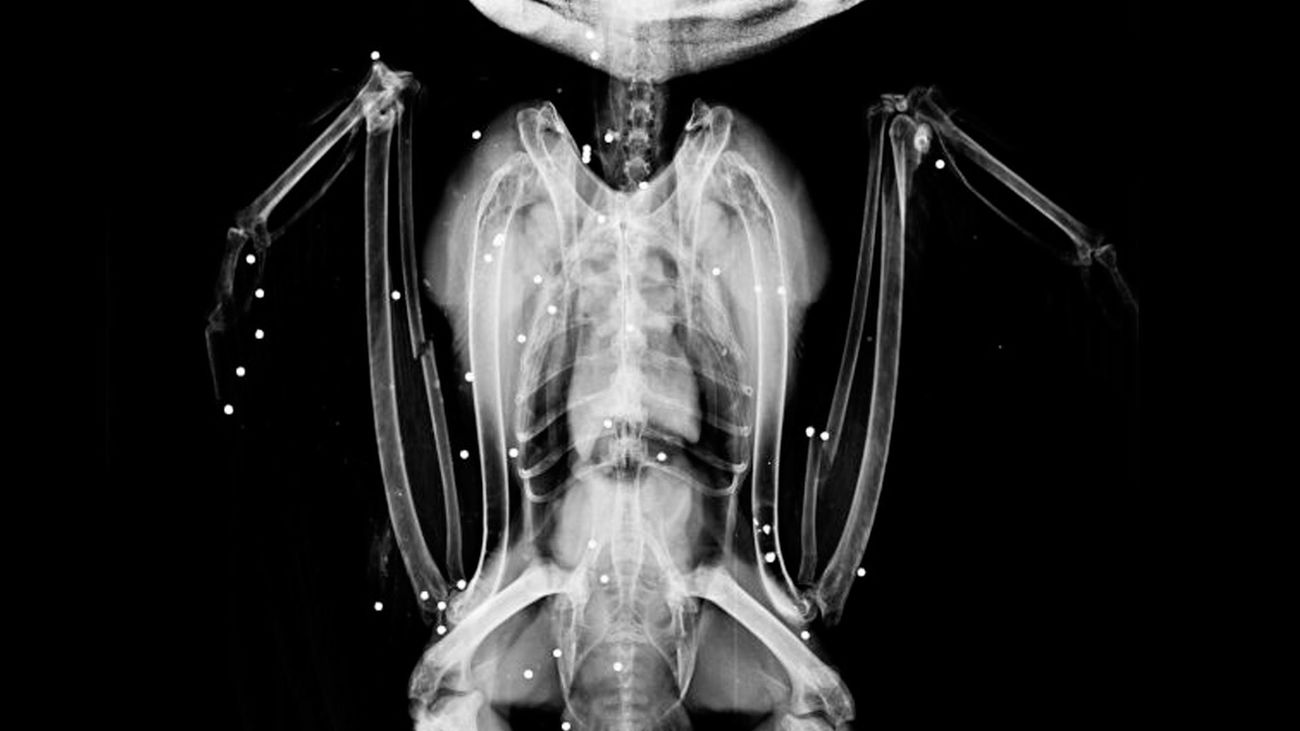

Radiografía del búho real tiroteado que entró en nuestro hospital de fauna

Radiografía del búho real tiroteado que entró en nuestro hospital de fauna |GREFA

Por su parte, el búho recibió el impacto de "más de 40 perdigones", por lo que ingresó en "estado crítico", y en estos momentos, según han indicado a Europa Press fuentes de la ONG, el animal está con "pronóstico reservado".